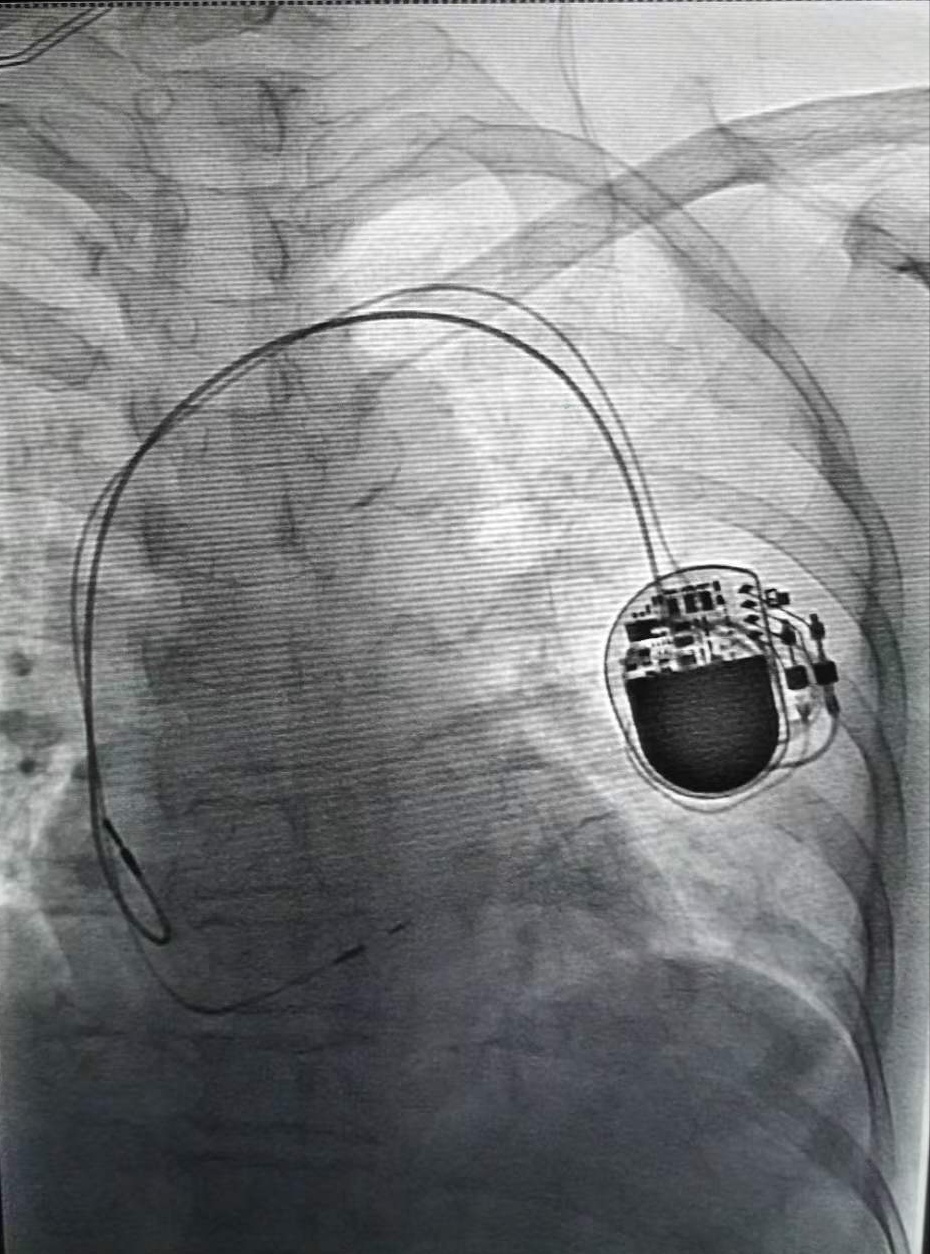

术中置入心脏起搏器

张大哥被家人紧急送到捷克论坛 ,医生查看心电图结果发现,他的心率只有32次/分(正常为60次/分到100次/分),Ⅲ度房室传导阻滞,情况十分危急,随时有心脏骤停、猝死及中风的危险,立即做好了遥测心电监护+床旁心电监护、除颤仪备用等急救准备,严密监测病情变化,同时准备为其手术安装心脏起搏器。因张大哥肋骨骨折及肺挫伤疼痛难忍,平躺坚持不了10分钟,心内三科主任潘宏伟、主任医师骆杨平、副主任医师钟常青团队综合考量,为张大哥制定了先急诊临时起搏救命,再尽快手术置入永久起搏器的方案。

钟常青副主任医师和起搏电生理手术团队争分夺秒,在张大哥仅平卧10分钟的间隙为其成功安装急诊临时起搏器,张大哥暂时转危为安,经过精心准备,又为其手术成功植入双腔永久起搏器。术后经过康复,11月30日,张大哥顺利出院。